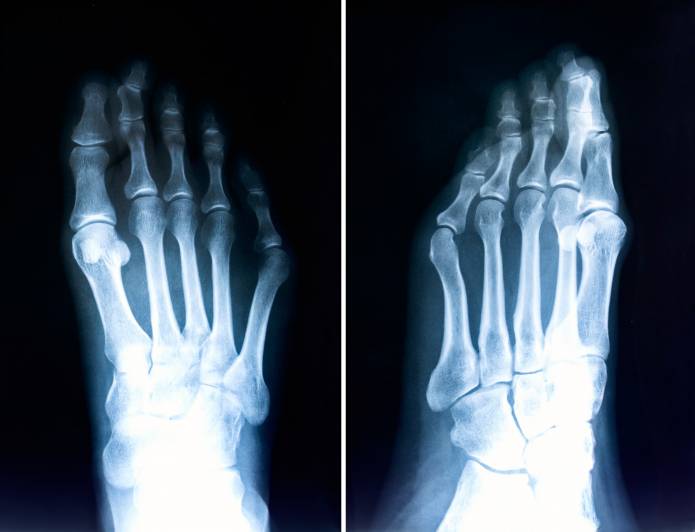

Die Diagnose der Hammerzehe oder Krallenzehe geschieht bereits durch den Anblick. Der Orthopäde befragt aber auch den Patienten hinsichtlich möglicher Ursachen und anderer Erkrankungen (Anamnese). Dann erfolgt die körperliche Untersuchung. Nicht nur die Verformungen mit veränderter Gelenkstellung, sondern auch Druckstellen und andere Fußveränderungen werden beurteilt. Röntgenbilder stützen die Diagnose und ermöglichen eine genauere Beurteilung. Röntgenaufnahmen sind zudem auch vorteilhaft, wenn eine Operation geplant werden soll.

Die Diagnose der Hammerzehe ist in der Regel sehr eindeutig. Der Arzt muss aber die verschiedenen möglichen Ursachen voneinander differenzieren. Meist sind schlechte Schuhe verantwortlich, aber beispielsweise sollte der Orthopäde auch neurologische (nervliche) Ursachen ausschließen.